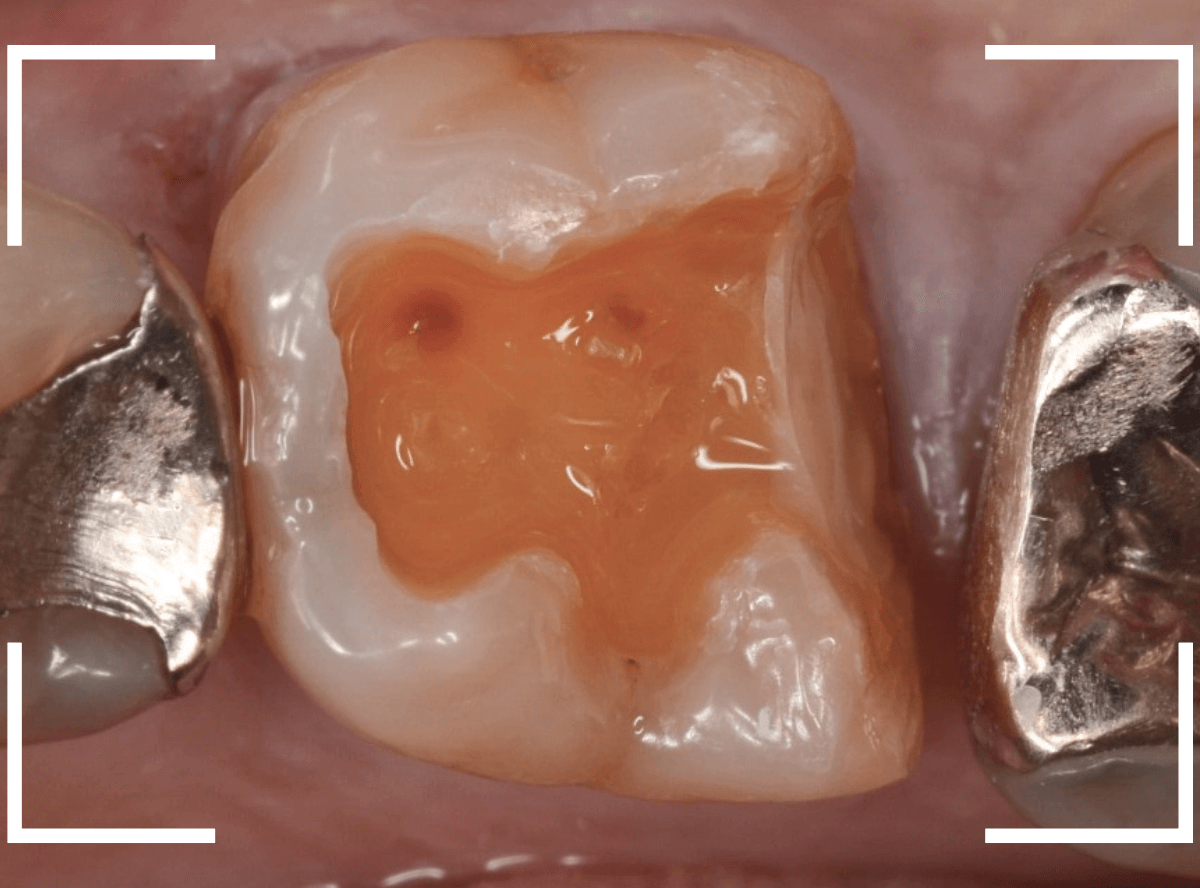

セラミックが精密にsetできるように、歯をトリミングします。

模型上で精密に製作します。

治療後の状態です。

ジルコニア・インレーはE-MAX・インレーより審美性に劣るのですが、患者さんにもご満足いただける仕上がりになり、ホッとしました。